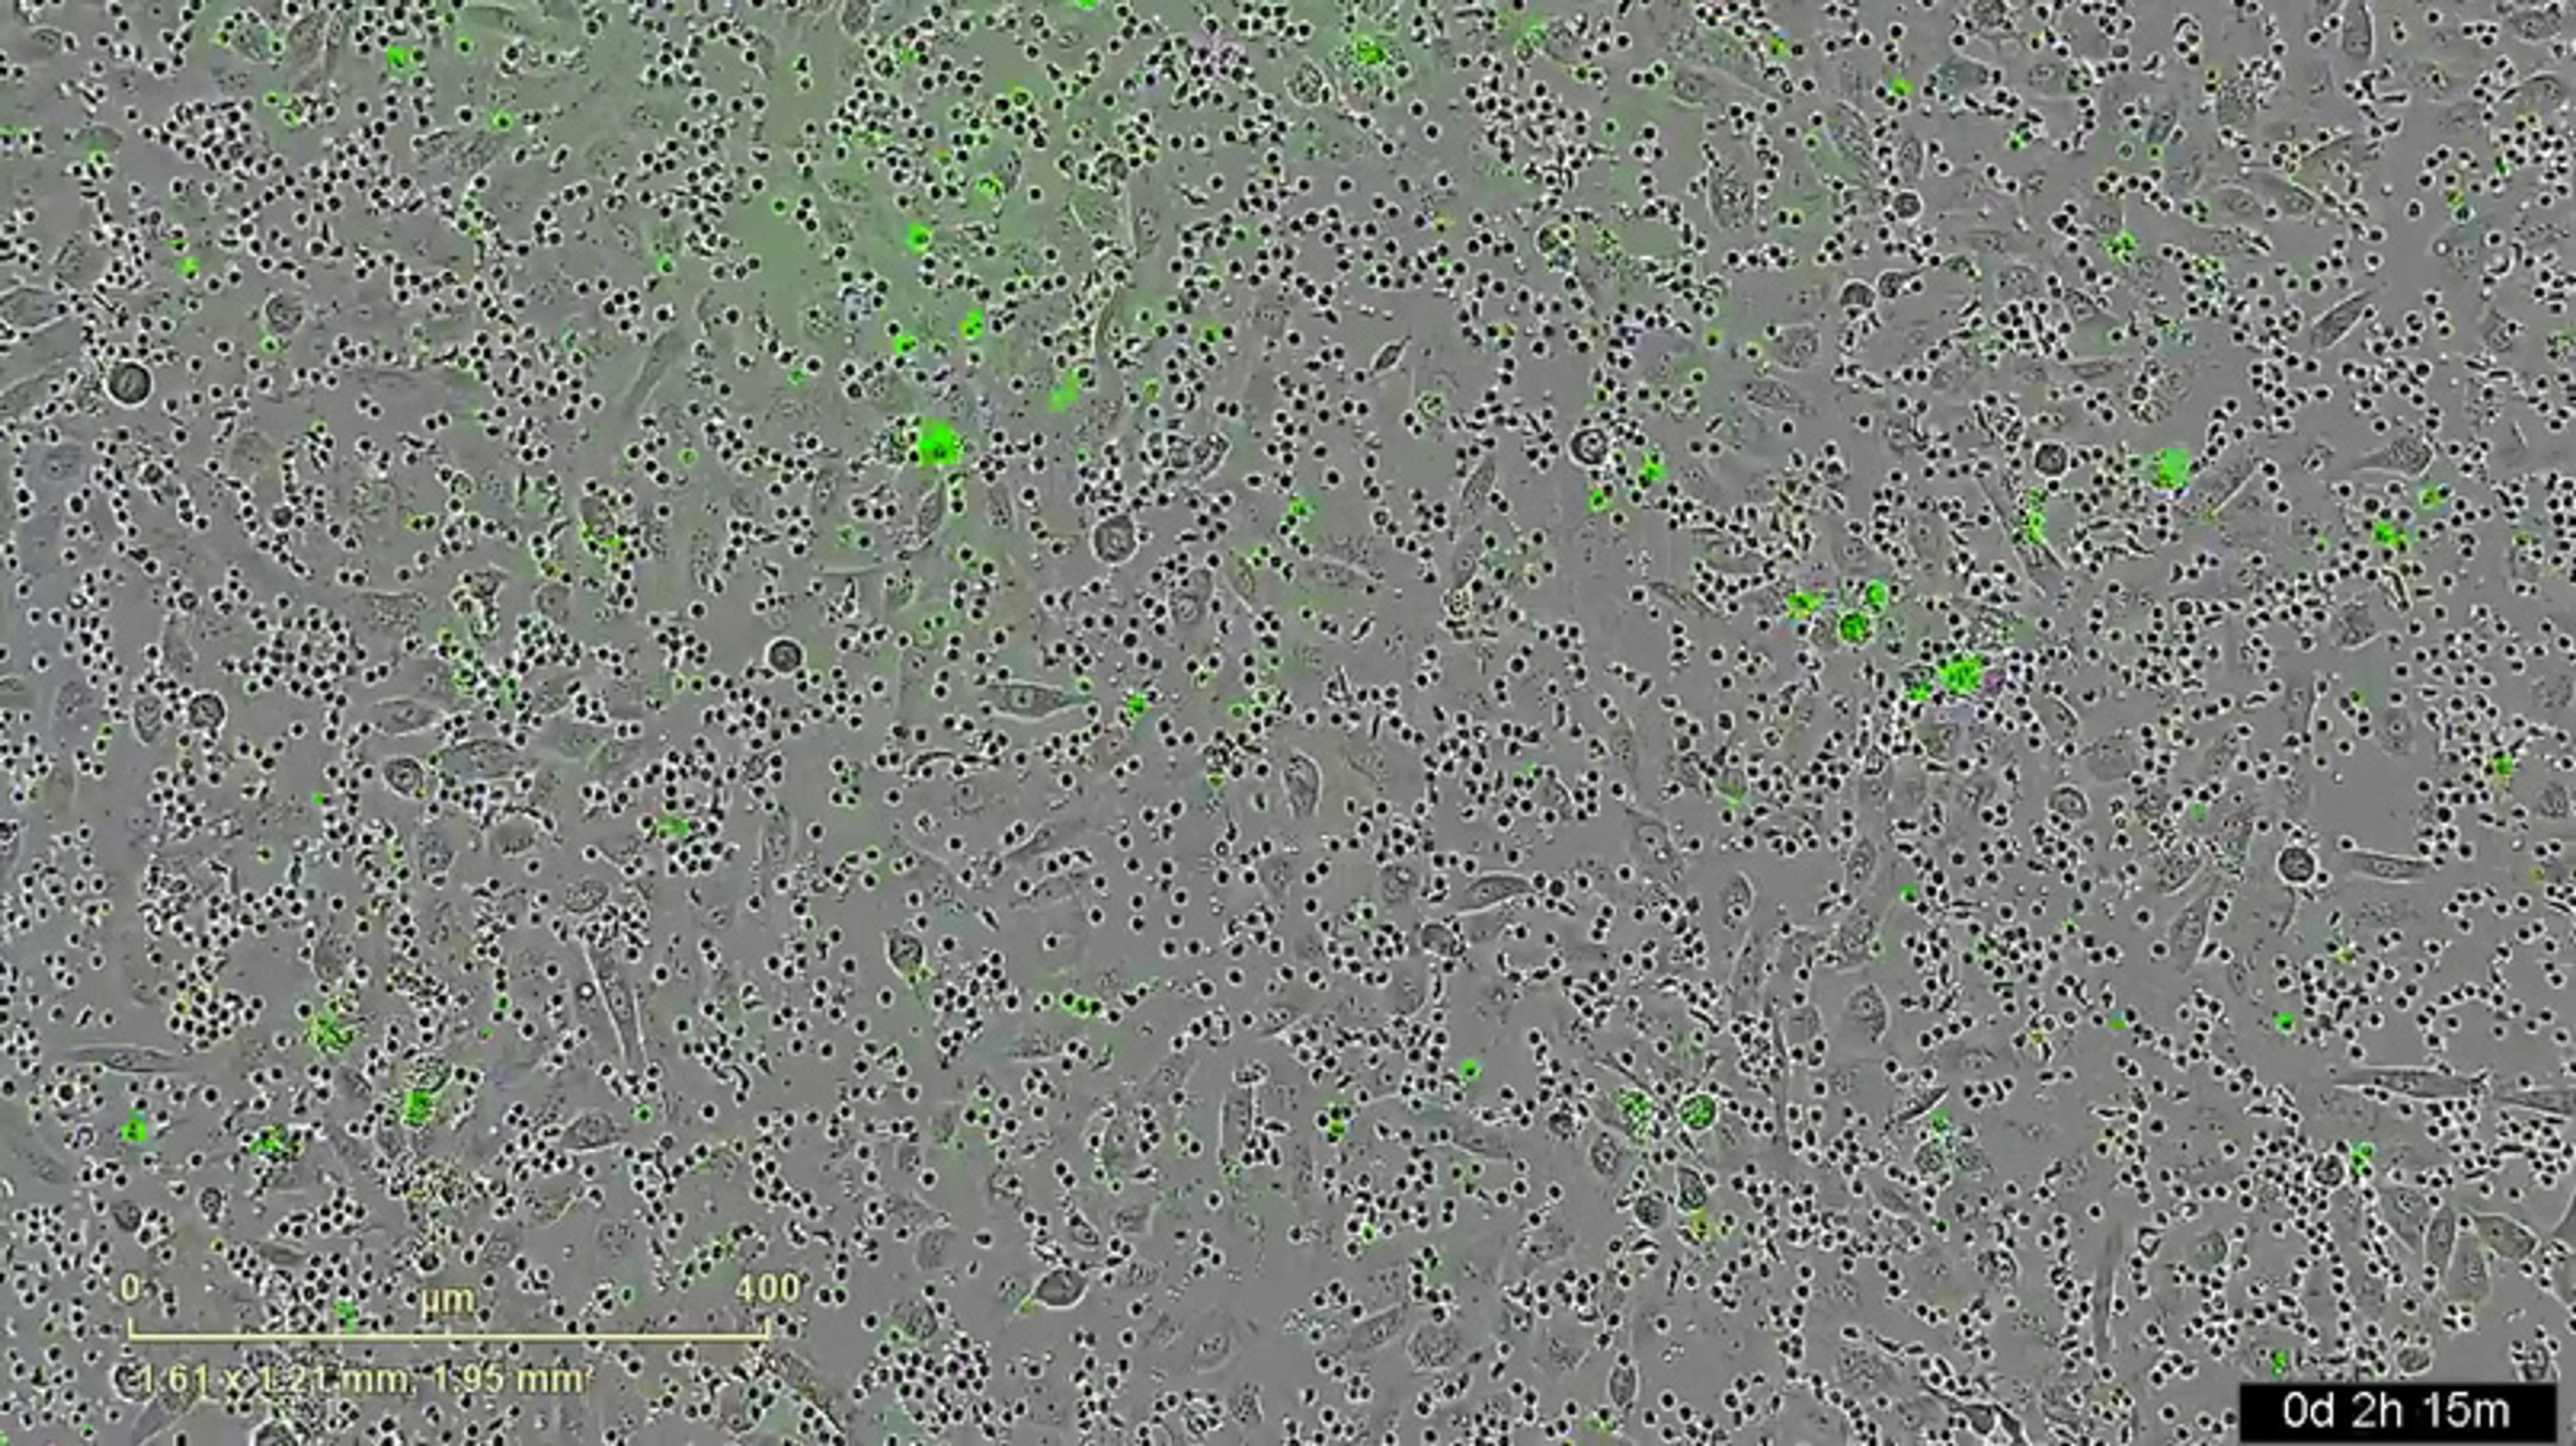

This video courtesy of Dr. Adam Case, shows mouse T cells (appearing as small black circles) killing pathogenic species, in this case, human cancer cells (appearing ovoid) in real time. The bright green fluorescent marker indicates cell death.